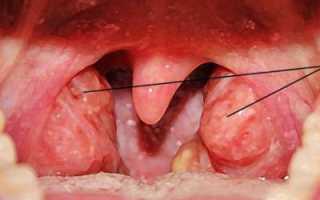

Нет нужды паниковать, болезнь только начинает проявляться. Возьмите зеркало, поднесите его ко рту и постарайтесь рассмотреть все тщательно.

Безусловно, вы можете хорошо увидеть малейшие оттенки недуга, более того именно вам под силу точно определить что же на самом деле являет проблема, и что с ней делать.

Вы можете найти небольшие пятна красноватого цвета, либо другие, более темные или белесые – это именно они являются причиной заболевания, а именно воспалительные процессы, которые возникают по причине инородных агентов.

Если болят гланды, следует пойти на прием к ЛОРу. Врач проверит миндалины, посмотрит, есть ли налет, прощупает их с внешней стороны. Бывает, пациенты интересуются: «Почему больше воспалена правая миндалина?»